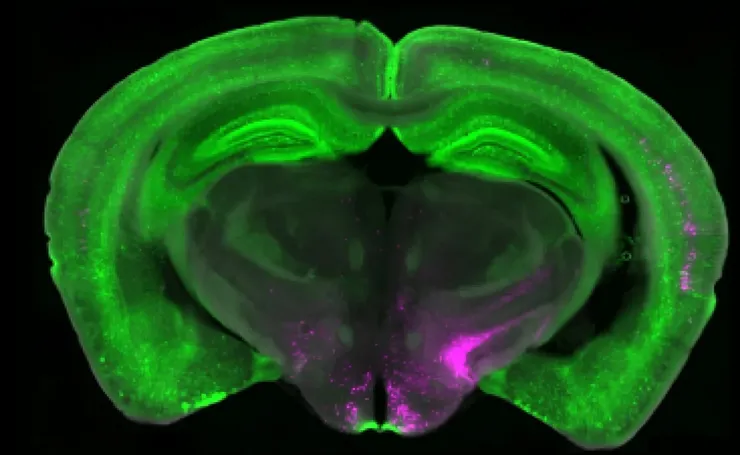

史丹佛大學生物學副教授陳曉可(Xiaoke Chen)帶領的團隊,在 3 月 31 日發表於《Nature》的研究中,找到了一條從來沒人描繪過的神經迴路。

它從脊髓出發,往上穿越丘腦和初級體感皮質,再往下鑽進腦幹裡的一個區域,最後又回頭連回脊髓,形成一個完整的閉合迴路。

研究團隊利用化學方式把這個迴路的節點關閉,結果原本對觸碰敏感的試驗鼠,開始只對真正的疼痛做出反應,對一般觸碰的過度反應消失了。

圖片來源:sciencedaily-Scientists discover brain circuit that can switch off chronic pain